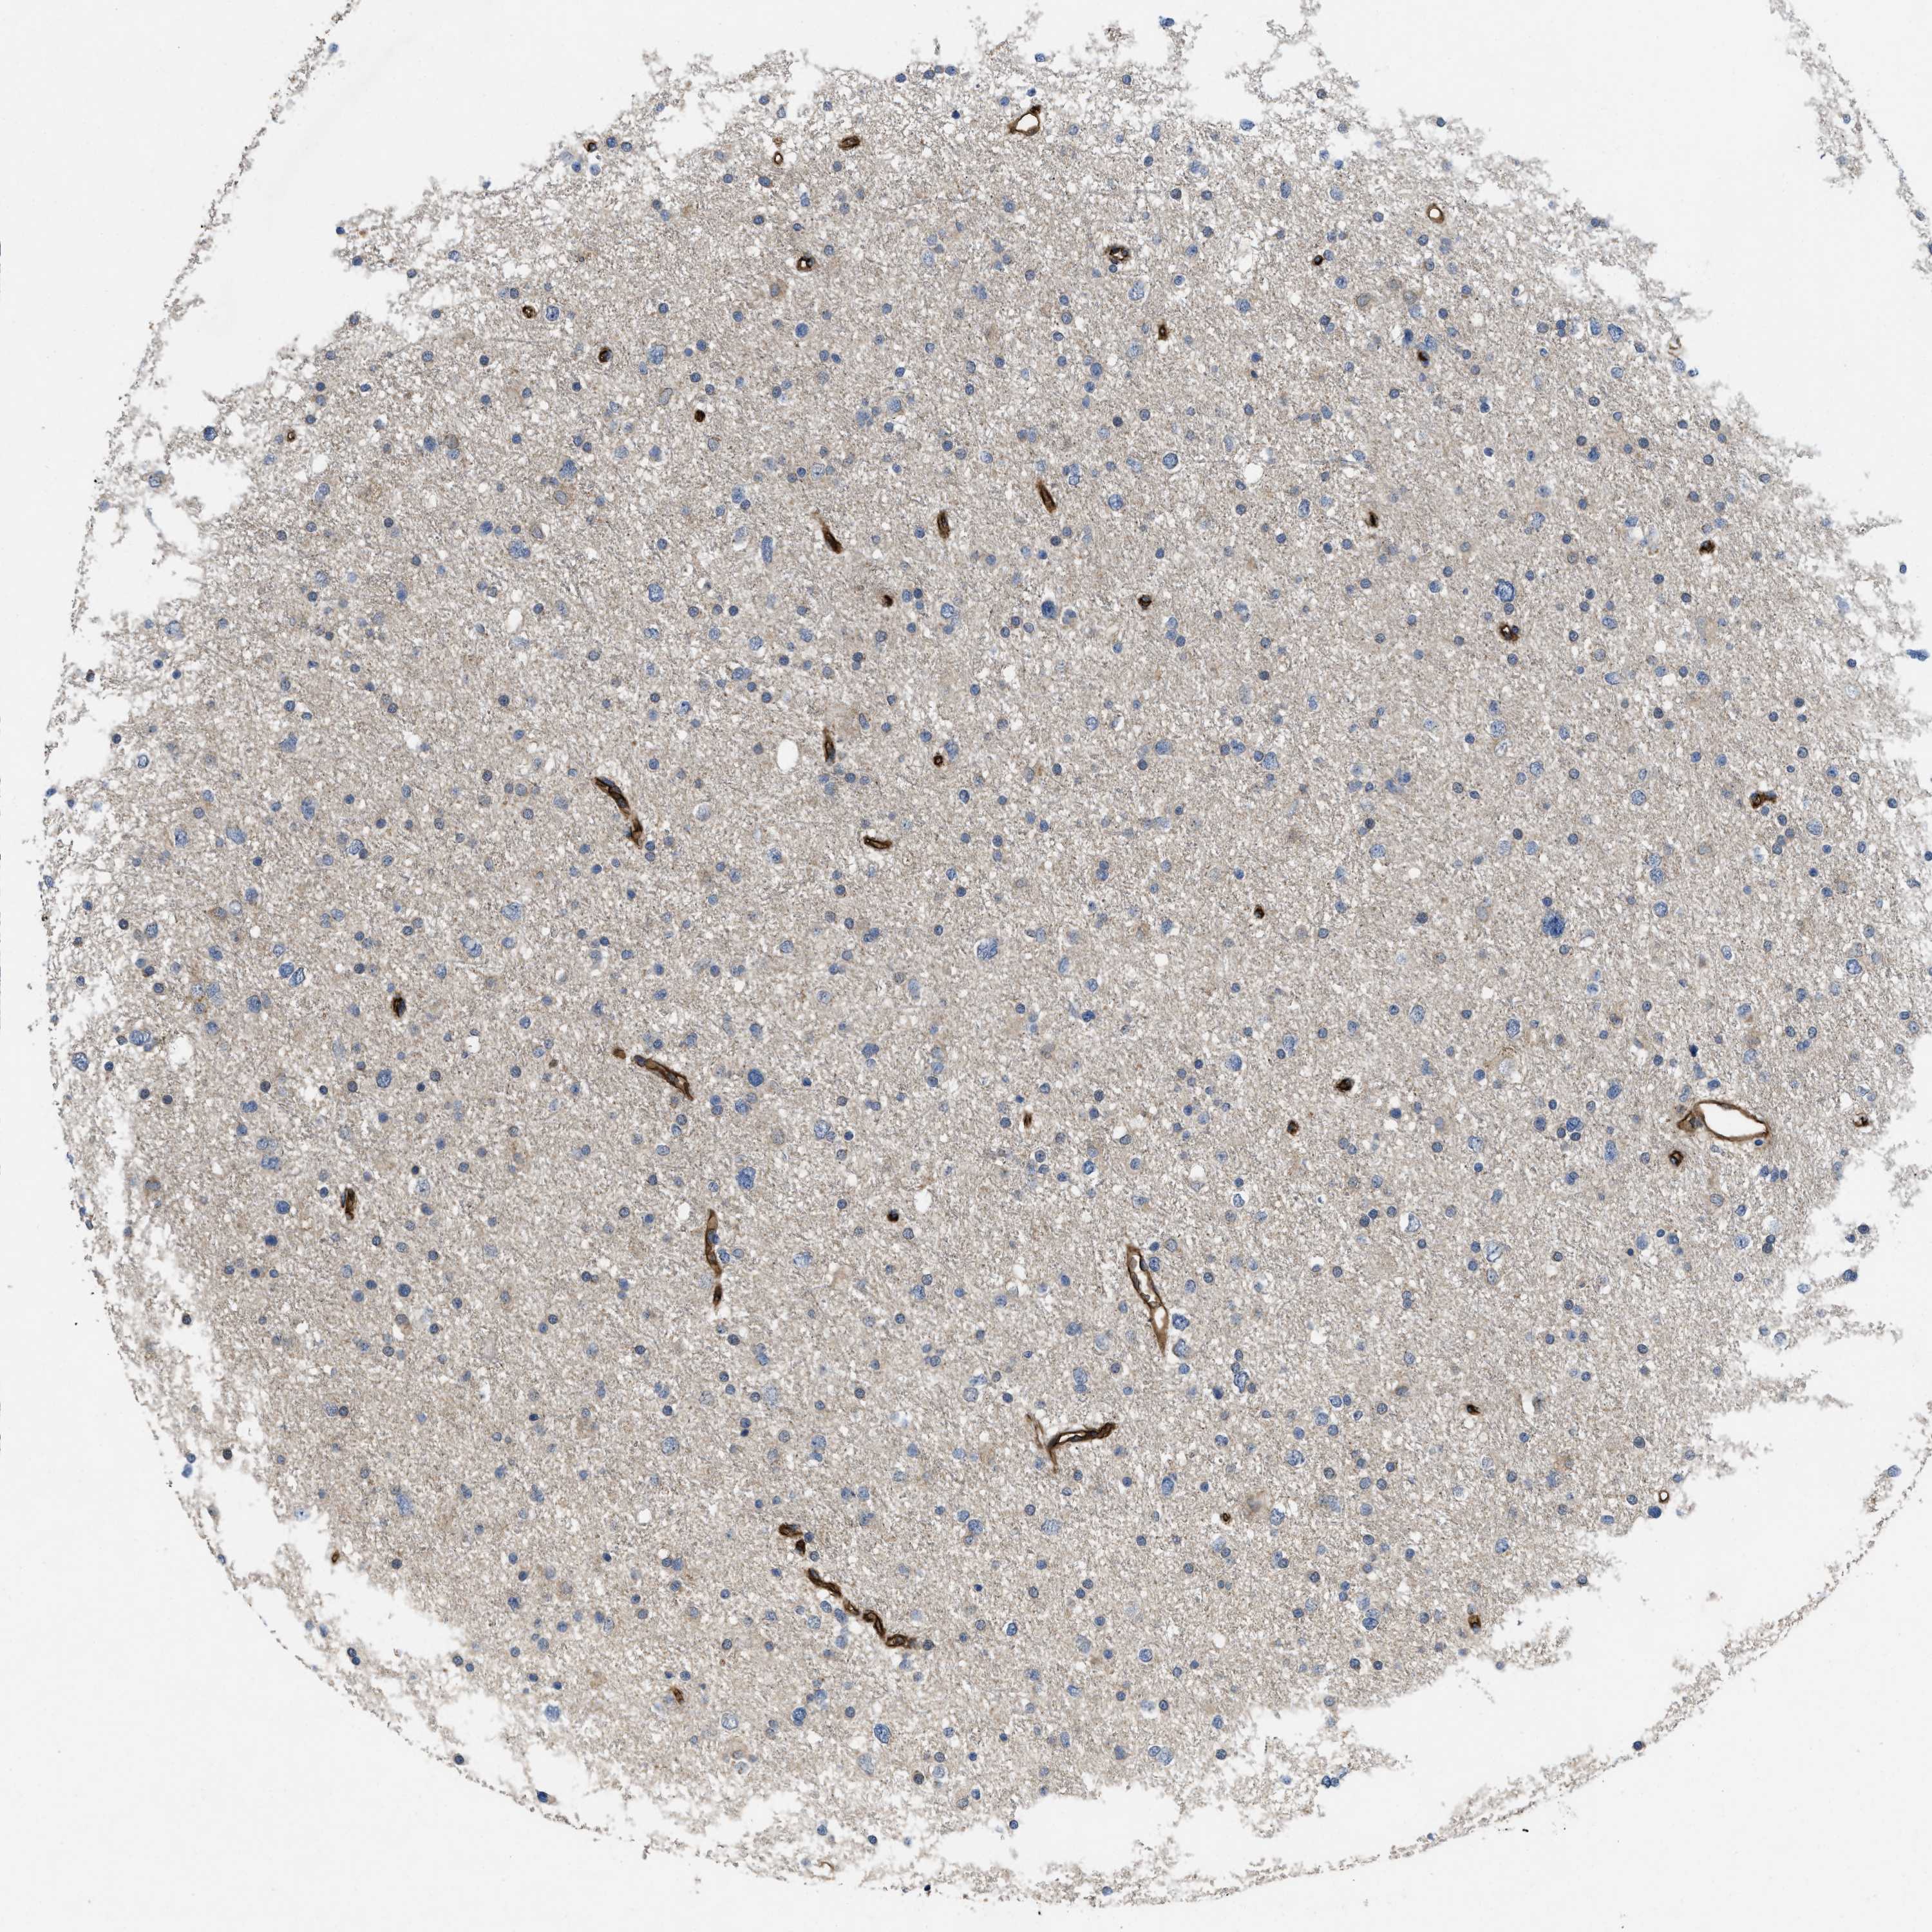

GLIOMA - Protein expressioni

A mouse-over function shows sample information and annotation data. Click on an image to view it in a full screen mode. Samples can be filtered based on level of antibody staining by selecting one or several of the following categories: high, medium, low and not detected. The assay and annotation is described here.

Note that samples used for immunohistochemistry by the Human Protein Atlas do not correspond to samples in the TCGA dataset.

Antibody stainingi

Antibody staining in the annotated cell types in the current human tissue is reported as not detected, low, medium, or high, based on conventional immunohistochemistry profiling in selected tissues. This score is based on the combination of the staining intensity and fraction of stained cells.

Each image is clickable and will lead to virtual microscopy that enables deeper exploration of all samples and also displays staining intensity scores, fraction scores and subcellular localization as well as patient and tissue information for each sample.

Antibody HPA013659

Antibody HPA015639

Glioma, malignant, High grade

Glioma, malignant, Low grade